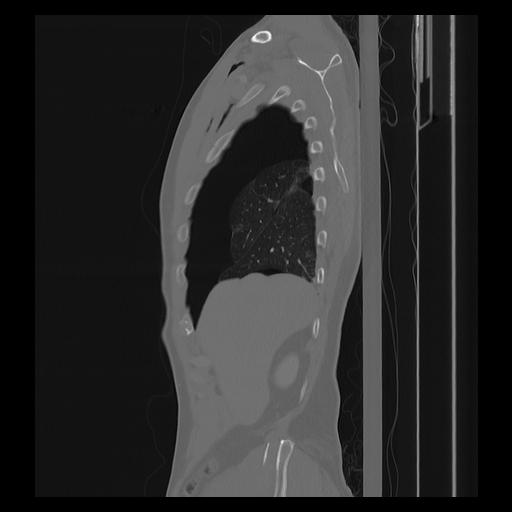

33 PULMON,CE,Sagittal,3.000,PULMON,Sagittal,